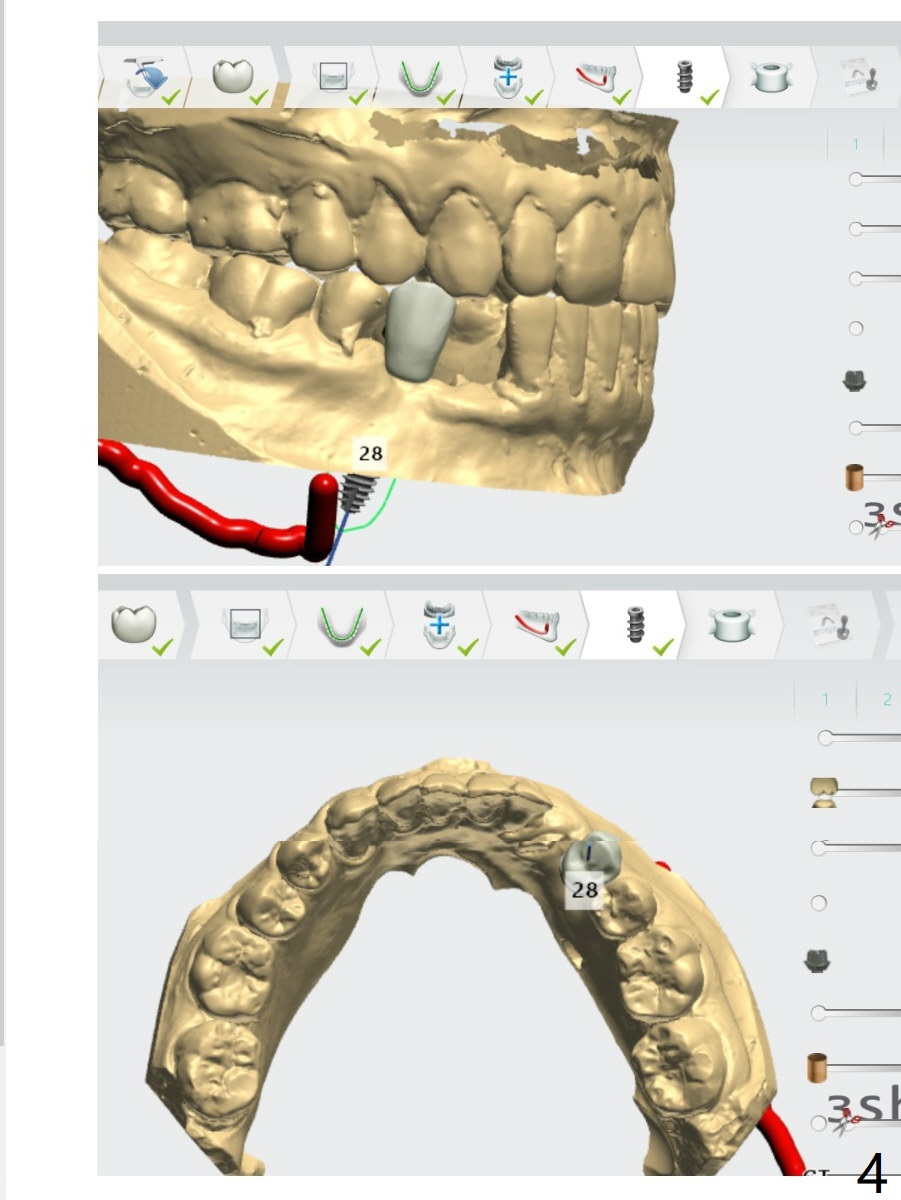

A 30-year-old man had the tooth #28 extracted with no bone graft. Allograft will be placed post implantation.

Lower Premolar

Immediate Implant,

Trajectory